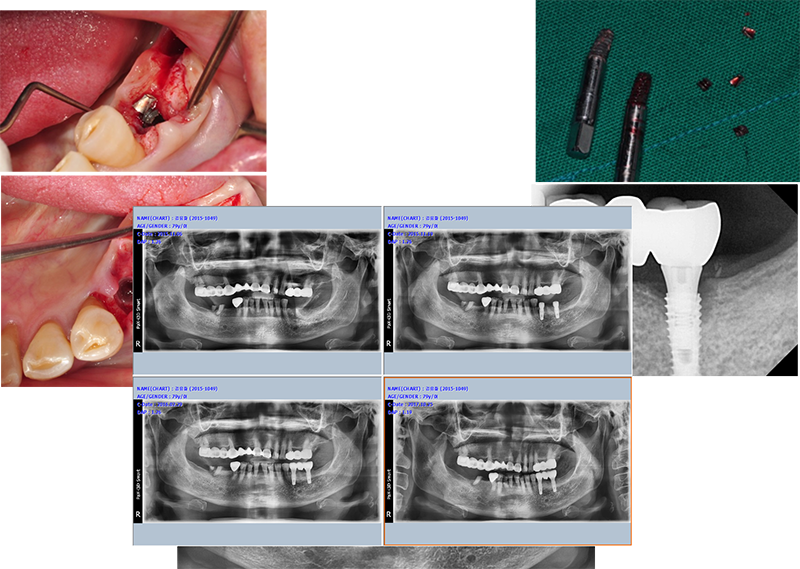

ÀÌ ÀÓ»ó ÄÉÀ̽º´Â ºê¸´Áö ŸÀÔÀ»

½Ì±Û ŸÀÔÀ¸·Î ¹Ù²ãÁÖ±â À§ÇÑ ÀÛ¾÷ Áß ÀÏ¾î³ ÀÛÀº ¼Òµ¿À» ±â·ÏÇß´Ù.

¾î¹þÀ» Ç®´Ù°¡ Ç÷¿Æû¿¡ ÀÖ´Â

Çí»ç°¡ ¸Á°¡Á³´Ù. Ç® ¼ö°¡ ¾ø¾ú´Ù. 4.4 mm ³»°æÀ» °¡Áø solid ab ü°á µå¶óÀ̺긦 ÀÌ¿ëÇϱâ·Î Çß´Ù.

¸ÕÀú Ezc ¾î¹þÀÇ Á÷°æÀ» ´ÙÀ̾Ƹóµå ¹ö·Î »ì¦ ´ÙµëÀº ´ÙÀ½, ½½·ÔÀ» ¸¸µé°í, À̰÷¿¡ solid ab µå¶óÀ̹ö°¡ »ðÀԵǵµ·Ï ÇÑ´Ù. µ¹¸®¸é ½±°Ô Á¦°ÅµÈ´Ù.

ÀÕ¸öÀÌ ¿ôÀÚ¶ú´Ù.